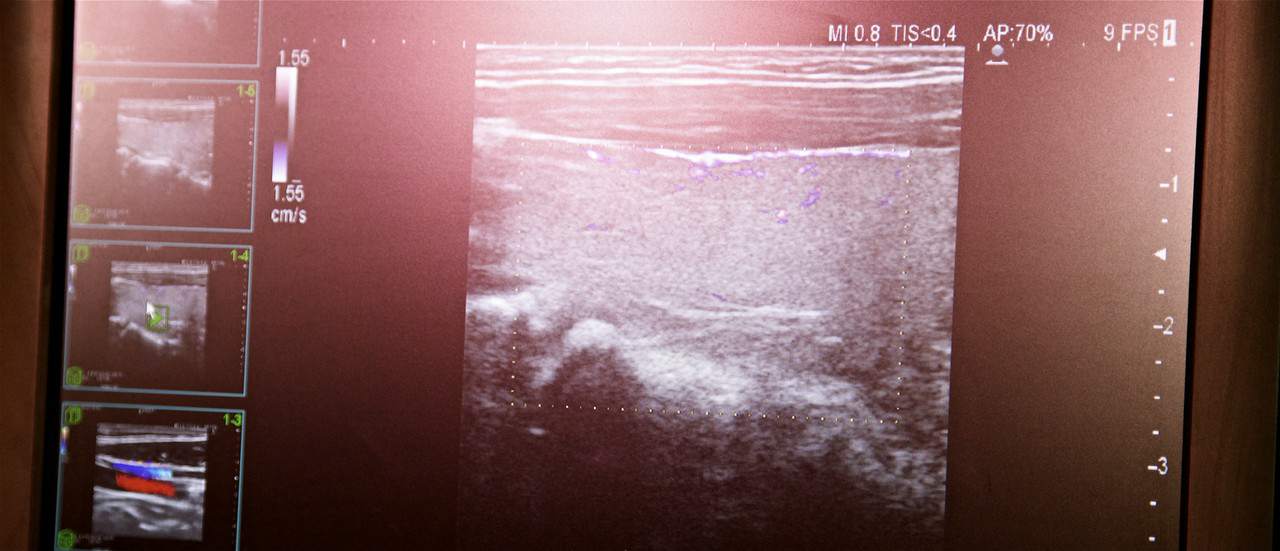

Lekarz przeprowadzi wywiad zdrowotny, a w razie potrzeby wykona też badanie, w tym USG tarczycy. Taka diagnostyka jest stosowana celem oceny wielkości gruczołu, a także wykrywania guzków i zmian ogniskowych w postaci torbieli oraz podejrzanych zmian. Co więcej, badanie USG może być zalecone pacjentowi w przypadku podejrzenia choroby Hashimoto.